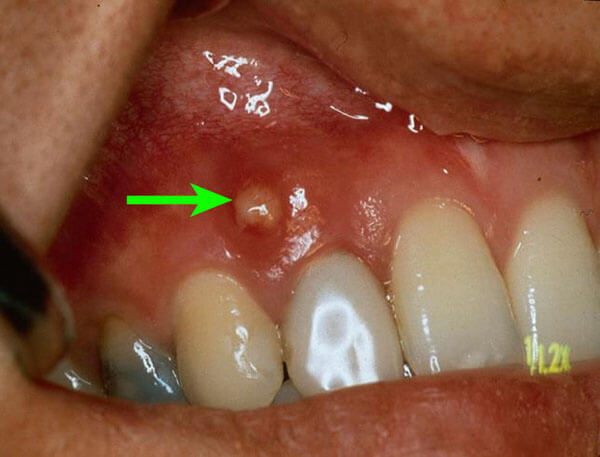

<歯根嚢胞に対する歯根端切除術+嚢胞摘出術>

歯の根の先に嚢胞ができ、歯茎に膿の出口を形成しています。